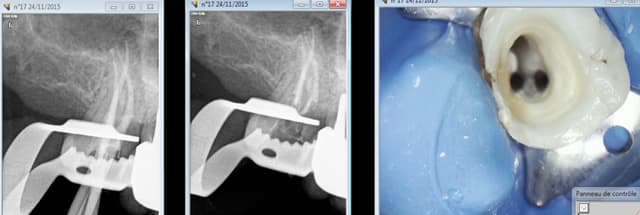

Capture d e cran 2015 11 24 23.14 - Eugenol

Tu dis rien en général, il ne se passe rien. C'est un aléa thérapeutique. Tu surveilles l'évolution éventuelle. Un apex en crochet par exemple ca arrive et à tout le monde endos exclusifs inclus ( moins peut etre parce qu'ils prennent leur temps et qu'ils font ca toute la journée)

Je paye une caisse de champagne à l'endo exclusif qui va me retirer ca par voie orthograde.-)))

Ca c'est à cause du localisateur d'apex, j'y étais mais ce con me disait que j'y étais pas tu insistes et paf. ( il a merdé sur l'autre canal d'ailleurs dépassement de 2 mm cone radio coupé de 2mm)

Capture d e cran 2015 11 25 13.18 - Eugenol